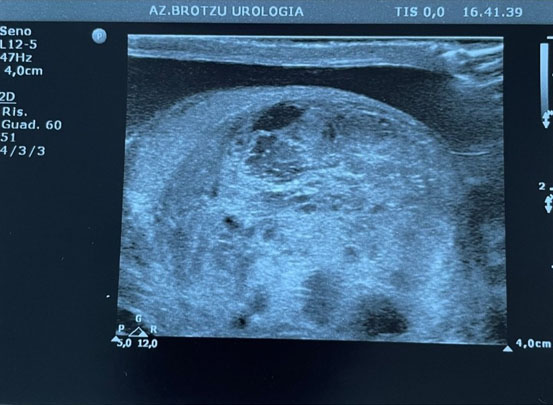

An 89-year-old man was admitted to the Department of Urology for testicular swelling and tenderness for five months with associated comorbidities of urolithiasis, atrial fibrillation in oral anticoagulant therapy, pleuritis, and hypertension. His testicular tumor markers [alpha-fetoprotein (AFP), beta-human chorionic gonadotropin (β-hCG), and lactate dehydrogenase (LDH)] were normal. A physical examination revealed a right testicular mass with normal skin and left testicle without abnormalities. Scrotal ultrasound (Figure 1) showed the presence of a large (4.16 × 2.26 cm) tumor with circular dichroism (CD) signal occupying the whole right testicle with heterogeneous echogenicity and smaller anechoic cystic components with minimal presence of normal testicular tissue. The left testicle was normal. A total-body computed tomography (CT) scan was performed and showed no signs of metastatic disease or lymphadenopathy. On suspicion of testicular cancer a right-sided radical orchiectomy was performed. Surgery was uncomplicated and he was discharged the day after the surgery. The patient had a close 12 month follow-up without need of any therapy and was in good condition 22 months after surgery.

Figure 1: Ultrasonic appearance of a right-sided tumor with far heterogeneously echogenic and cystic areas.